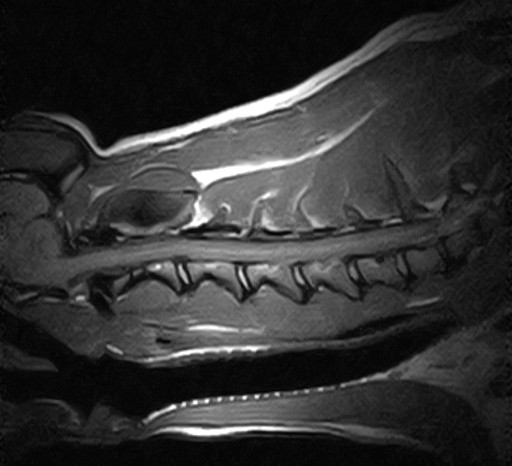

W obrębie kanału kręgowego najczęstszymi wskazaniami do badania rezonansem magnetycznym u zwierząt są:

• ocena rdzenia kręgowego, splotów i nerwów rdzeniowych

• zwyrodnieniowe zwężenie lędźwiowe krzyżowe (DLSS)

• spondylomielopatia szyjna

• malformacje Chiariego

• wady złącza czaszkowo mózgowego